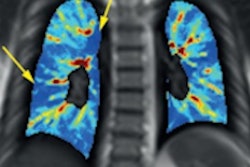

On ultrasound, vapers and smokers had lower flow-mediated dilatation (FMD%) of the brachial artery compared with their nonsmoking counterparts (5.4% vs. 7.9%).